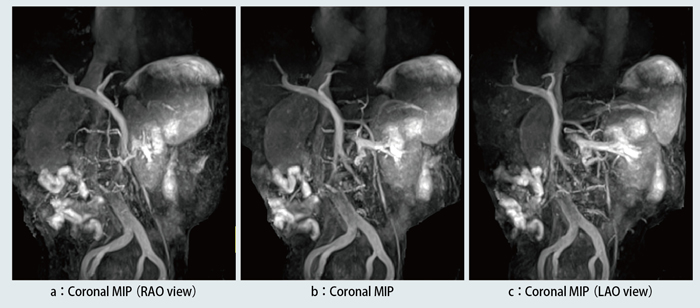

門脈のMRAは,主に門脈圧亢進症における側副血行路の描出を目的に行われる。撮像条件は,TR/TE:3.6/1.6ms,FA:120°,FOV:380mm×380mm,Matrix:256×256,Slab:90mm,Spatial resolution:1.5mm×1.1mm×1.5mm,Scan plane:Coronal,Parallel imaging reduction factor:2.0,Trigger:Respirator,Fat saturation:CHESS TI:1500msと固定している。腹部全体をカバーする領域にIR pulseを印加し,撮像範囲の縦磁化を反転する。脾静脈や上腸間膜静脈を含む領域に斜めのIR pulseを印加することで,その領域の縦磁化を戻し,縦磁化が戻された領域からTI(1500ms)時間移動した血流のみが,肝臓に流れこんだ門脈血流として描出される。さらに,骨盤部の静脈やIVCを抑制する目的でIR pulseを2回印加する(図5)。症例3は,InferiorにIR pulseを印加していないため,IVCが描出されている(図6)。症例4は,InferiorにIR pulseを2回印加しているので,IVCが抑制されている(図7)。しかし,側副血行路を描出するには,撮像領域が肝臓から骨盤部までと広範囲になるため,胃や小腸の水の信号,胆嚢や脳脊髄液など高信号となる領域の信号を抑制することが今後の課題である。

図7 症例4:門脈圧亢進症における側副血行路の描出(InferiorにIR pulseあり)